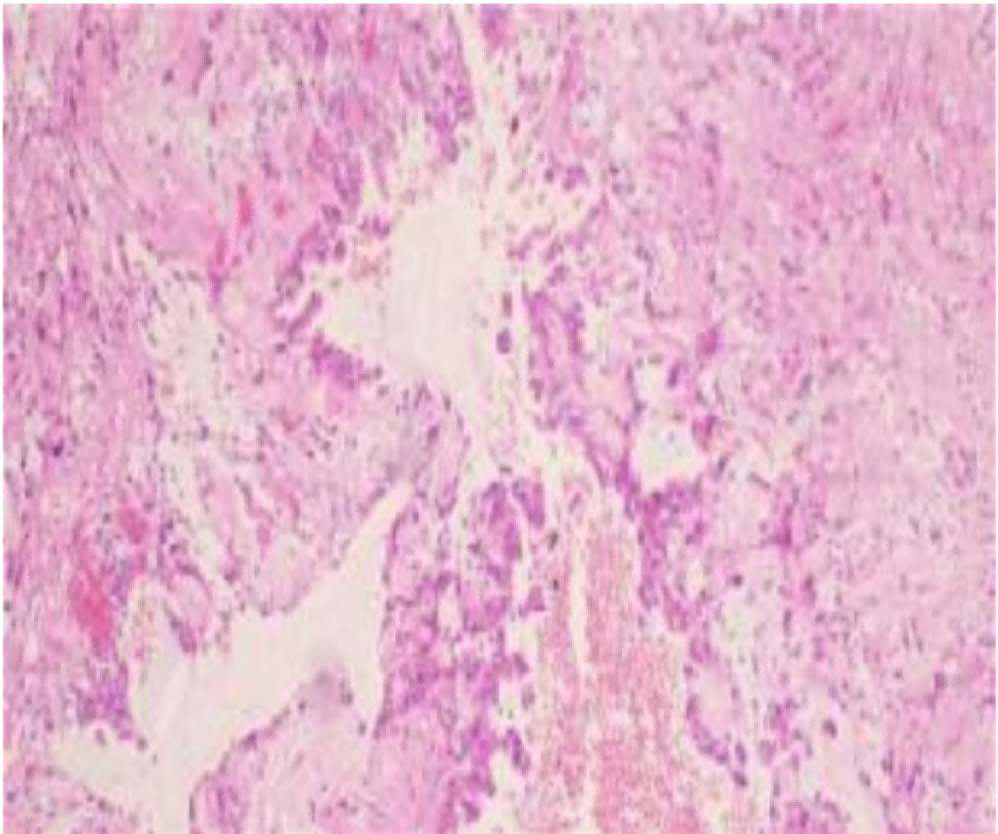

(左顶叶占位)低级别胶质瘤伴Rosenthal纤维增生,结合HE形态及免疫组化结果首先考虑幕上毛细胞型星形细胞瘤(WHO 1级)

免疫组化染色结果:

<第1次>B(左顶叶占位常规):IDH

1(+)、MGMT(+)、H3K27M(-)、CD34(血管+)、CK(Pan)(-)、01igo-2(+)、SYN(+)、EGFR(-)、Ki-67(约 5%)、GFAP(+)、Vimentin(+)、P53(野生型)、S-100(+)、SSTR

2(灶+)、EMA(灶+)、CD99(灶+)、CK7(-)、D2-40(+)。

<第2次>B(左顶叶占位常规):ATRX(+)、BRAF(—)、BRAF—PC(阳性对照正常表达)。